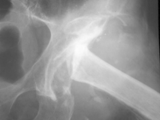

AVN-femur

AVN-femur